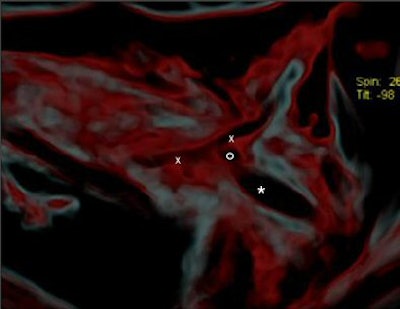

![]() |

| CT image shows the injury (x-x) and the head of the arrow (*). Figure published in: JArcheol Sci, in press, Pernter P., Gostner P., Egarter Vigl E., Rühli, F. J., "Radiologic proof for the Iceman's cause of death (ca 5300 BP), Copyright Elsevier. Image courtesy of Dr. Frank Rühli and the University of Zurich, Switzerland. |

"It seems most likely that (the arrowhead) lacerated the subclavian artery. By removing the shaft of the arrow perimortem, its head must have been slightly retracted to the actual position where the barbs caught in the tissue and, eventually, the arrowhead separated from the now missing shaft," the group wrote. "In the surrounding soft tissue one can see linear air incorporations as well as multiple irregular partially confluent densities (-80 HU), with the latter likely representing a hematoma. It spreads dorsocaudally between the ribs and the scapula, and also into the shooting channel toward the subcutaneous soft tissues" (Journal of Archaeological Science, March 15, 2007).